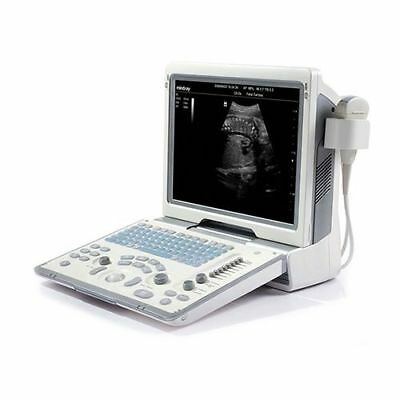

MINDRAY DP-50 ULTRASOUND SYSTEM WITH ONE TRANSDUCER

The Mindray DP-50 Ultrasound System comes with one transducer and offers high-quality imaging for a wide range of clinical applications. Known for its advanced technology, the DP-50 provides clear, accurate diagnostic results for obstetrics, gynecology, abdominal, and other general imaging needs. The system is user-friendly, with an intuitive interface that simplifies operation. Its compact design ensures portability, making it ideal for use in both hospitals and clinics. The Mindray DP-50 is a reliable, efficient ultrasound system for healthcare professionals seeking precision in patient care.